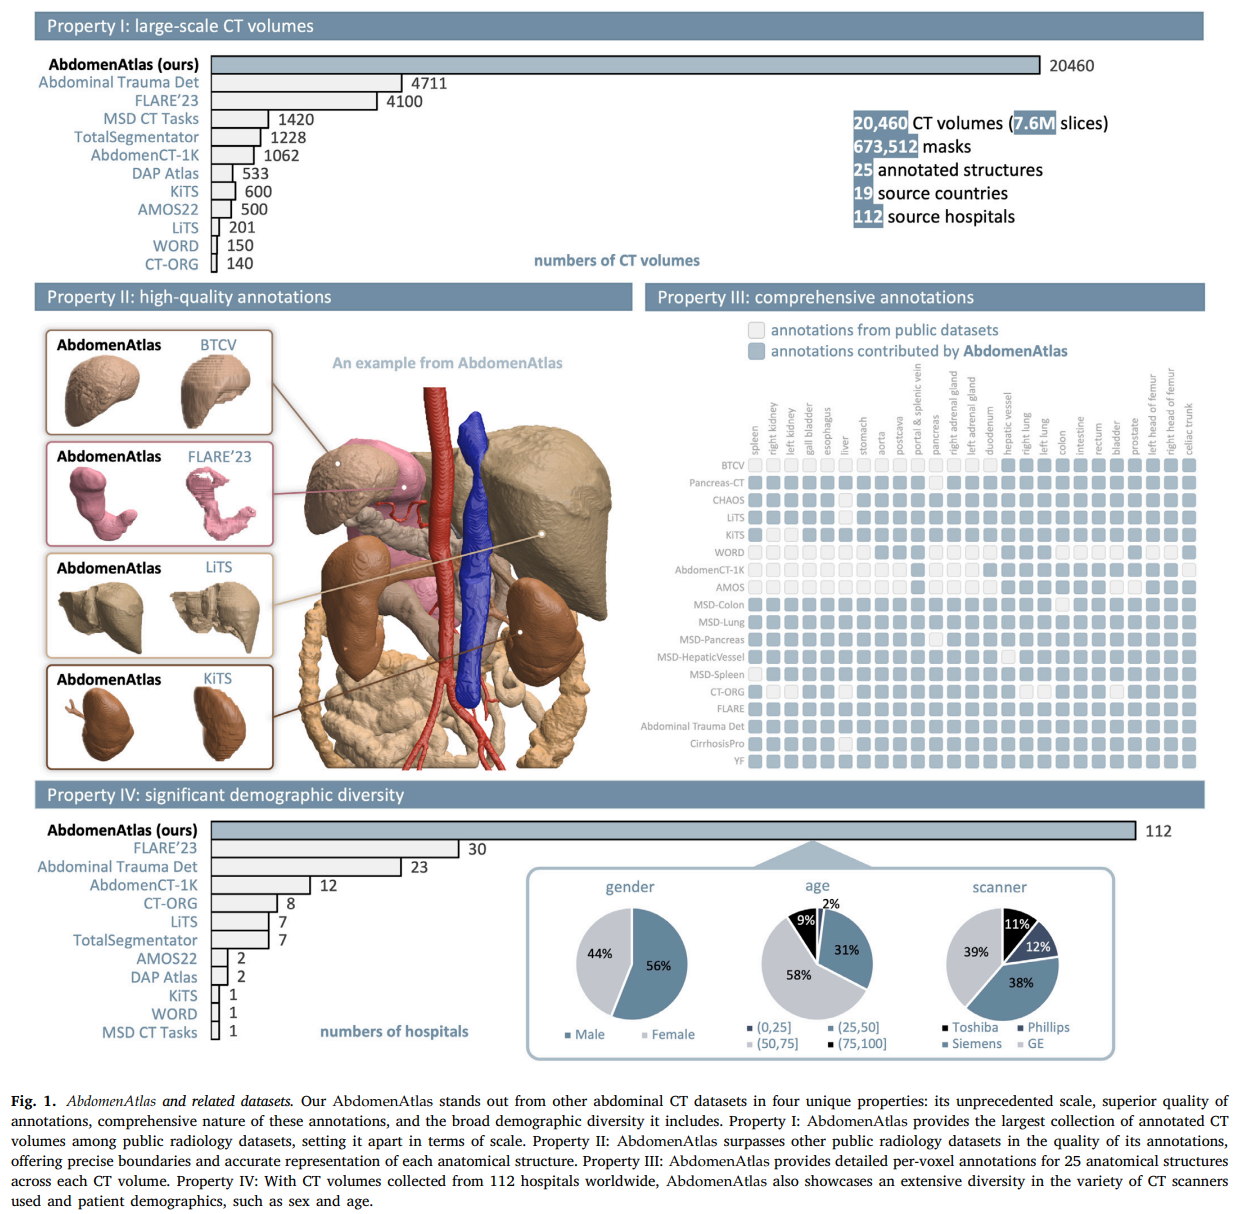

大规模、多中心数据集:本文介绍了迄今为止最大的腹部CT数据集(AbdomenAtlas),包含来自112家医院的20,460个三维CT体积,涵盖了不同人群、地理区域和设施。该数据集提供了673,000个高质量的腹部区域解剖结构掩码,这些掩码由10名放射科医生在AI算法的帮助下进行注释。

我们介绍了迄今为止最大的腹部CT数据集(称为AbdomenAtlas),包含来自112家医院的20,460个三维CT体积,涵盖了不同人群、地理区域和设施。AbdomenAtlas提供了673,000个高质量的腹部区域解剖结构掩码,这些掩码由10名放射科医生在AI算法的帮助下进行注释。我们首先由专家放射科医生手动注释了5,246个CT体积中的22个解剖结构。随后,对剩余的CT体积进行了半自动注释程序,放射科医生修订了AI预测的注释,而AI则通过学习修订后的注释来改进其预测。如此大规模、详细注释和多中心的数据集有两个主要原因。首先,AbdomenAtlas为大规模AI开发提供了重要资源,特别是作为大型预训练模型,可以减轻专家放射科医生的注释工作负担,并将其转移到更广泛的临床应用中。其次,AbdomenAtlas为评估AI算法建立了一个大规模的基准——我们使用的数据越多,越能保证算法在复杂临床场景中的可靠性能。我们使用AbdomenAtlas的一个子集发起了名为BodyMaps的ISBI和MICCAI挑战赛,旨在刺激AI创新,并基准测试分割精度、推理效率和领域泛化能力。我们希望AbdomenAtlas能够为更大规模的临床试验奠定基础,并为医学影像社区的从业者提供卓越的机会。代码、模型和数据集可在https://www.zongweiz.com/dataset获取。

本文并不打算讨论如何在医学影像中创建类似GPT的视觉模型,而是致力于提供可能催化此类讨论所需的数据和注释。我们收集并注释了20,460个CT体积,总计673,000个高质量的腹部区域解剖结构掩码。这些CT体积来自112家医院,分布在19个国家,使得这一努力在规模上前所未有。这是迄今为止最大规模的医学数据集,用于AI基准测试,并有望成为医学领域大型预训练模型开发的宝贵资产。我们将此数据集命名为AbdomenAtlas。需要来自不同中心的大规模数据集有两个主要原因:(I)已知AI算法的性能在训练数据越多时越好;我们使用的数据越多,越能保证算法在现实世界条件下(例如临床环境)的良好性能。(II)在不同中心的数据上训练和测试AI算法至关重要,因为AI研究人员发现,在一个中心的数据上训练的算法可能无法泛化到其他中心的数据(如DeGrave等(2021)和Geirhos等(2020)所示)。

2.2.1 属性I:大规模CT体积

AbdomenAtlas提供了20,460个注释的CT体积,如图1-属性I所示,关联了超过760万注释的CT切片。除了提供AbdomenAtlas的详细信息外,表1还展示了其组件和用于训练(AbdomenAtlas 1.1)和测试(FullBodyAtlas-1K和AbdomenAtlas-9K)的细分。AbdomenAtlas不仅代表了用于AI训练的医学数据的显著增加,还作为AI基准测试的广泛资源。在AbdomenAtlas中,9,262个注释的CT体积将在AbdomenAtlas 1.1中公开,用于AI算法的开发,而1,761个注释的CT体积已经在FullBodyAtlas-1K中公开,用于算法基准测试,这要归功于TotalSegmentator(Wasserthal等,2022)和DAP Atlas(Jaus等,2023)。此外,我们已经组装并注释了来自15家医院的9,437个CT体积,称为AbdomenAtlas-9K,这些数据将保留用于严格的外部验证。AbdomenAtlas的规模——20,460个CT体积和673,000个掩码——使得开发和评估适用于广泛医学影像任务的AI算法成为可能。

创建673,000个高质量的25个解剖结构掩码需要广泛的医学知识——至少需要三年的解剖结构培训,以及显著的注释成本——每个结构大约需要放射科医生一小时的时间来注释(Park等,2020)。如第3.1节所述,我们基于人体解剖学(Dixon等,2017)建立了严格的注释标准,以指导放射科医生准确注释或修订每个结构,确保质量控制。该标准在保持我们注释质量方面的有效性如图1-属性II所示,其中AbdomenAtlas中的注释显示了精确的边界和准确的解剖结构分割,与BTCV、FLARE’23、LiTS和KiTS中的注释相比。

2.2.3 属性III:全面注释

如图1-属性III所示,我们为25个解剖结构提供了全面的逐体素注释,确保了一个完全标注的数据集,而不是从公共数据集的简单组合中得到的部分标注数据集。值得注意的是,与仅包含39,000个掩码的组合不同,我们的AbdomenAtlas 1.1为这些CT体积提供了231,000个注释的结构掩码,显著增加了5.9倍的可用掩码。这一增加不仅增强了数据集的实用性,还使得在医学影像分析中进行大规模、监督的(预)训练成为可能。

2.2.4 属性IV:显著的人口多样性

AbdomenAtlas是一个多中心数据集,包含来自112家全球医院的预、门、动脉、静脉和延迟期CT体积。如图1-属性IV所示,AbdomenAtlas展示了人口多样性,患者性别分布均衡,女性占56%,男性占44%,年龄范围广泛。值得注意的是,58%的患者年龄在25至50岁之间,31%在50至75岁之间,9%在25岁以下,2%在75岁以上。此外,AbdomenAtlas包括来自不同扫描仪的CT体积,如西门子、GE、飞利浦和东芝,并涵盖了16/64层MDCT和双源MDCT的CT体积。这些多样性在期相、医院、国家、人口统计、扫描仪和扫描类型方面丰富了AbdomenAtlas,确保使用AbdomenAtlas开发的AI算法能够有效处理不同成像协议或患者体位引起的结构外观变化,例如沿垂直轴旋转30至60度。研究表明,训练数据的多样性是AI分布鲁棒性的关键(Fang等,2022)。因此,AbdomenAtlas的多样性有助于开发能够适应现实世界临床环境中多样化设置的鲁棒、公平和可泛化的AI算法。